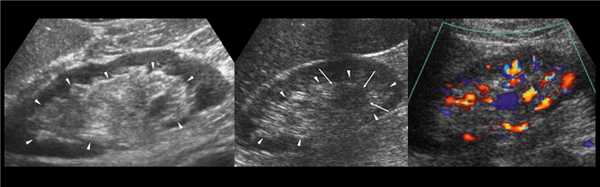

Чтобы увидеть верхний полюс почки, попросите пациента сделать глубокий вдох. Форма почки бобовидная — выпуклая с латеральной и вогнутая с медиальной стороны. Как вариант нормы расценивают эмбрионально-дольчатую почку, а так же горбатую левую почку.

Рисунок. На УЗИ (1) и КТ (2, 3) контур почек волнистый. У эмбриона почка развивается из отдельных долек, которые сливаются по мере их роста. Дольчатое строение почек хорошо видно у плода и новорожденных, в единичных случаях сохраняется у взрослых.

Рисунок. Можно встретить горбатую левую почку — выпуклый неровный наружный контур из-за гипертрофии паренхимы в средней трети почки. Считают, что «горб» формируется у плода под давлением нижнего края селезенки.